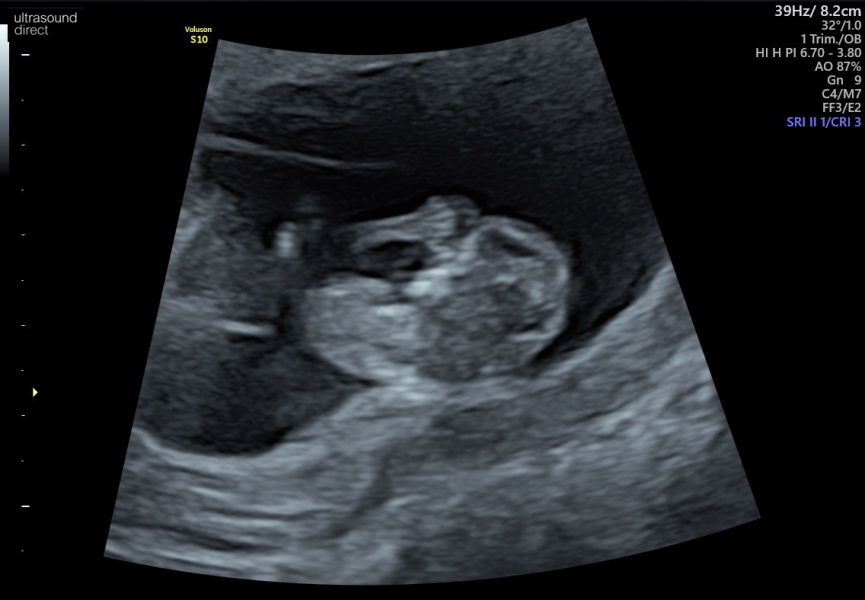

Oh and because it's cute we got a image of baby's tiny little fingers ❤️

@Gardenlady543 hello baby!!! ItMs waving at us! Is this another scan or a pic from the other day!

@Gardenlady543 what a gorgeous scan, so nice to see the fingers! Glad things are going well with scans and results.

Thanks guys :) this is from yesterday's scan :) the videos I got weren't that great as the probe was moving but I got this cute picture. My NIPT results just came through and I'm having a girl! me and my husband have always wanted a girl!!!